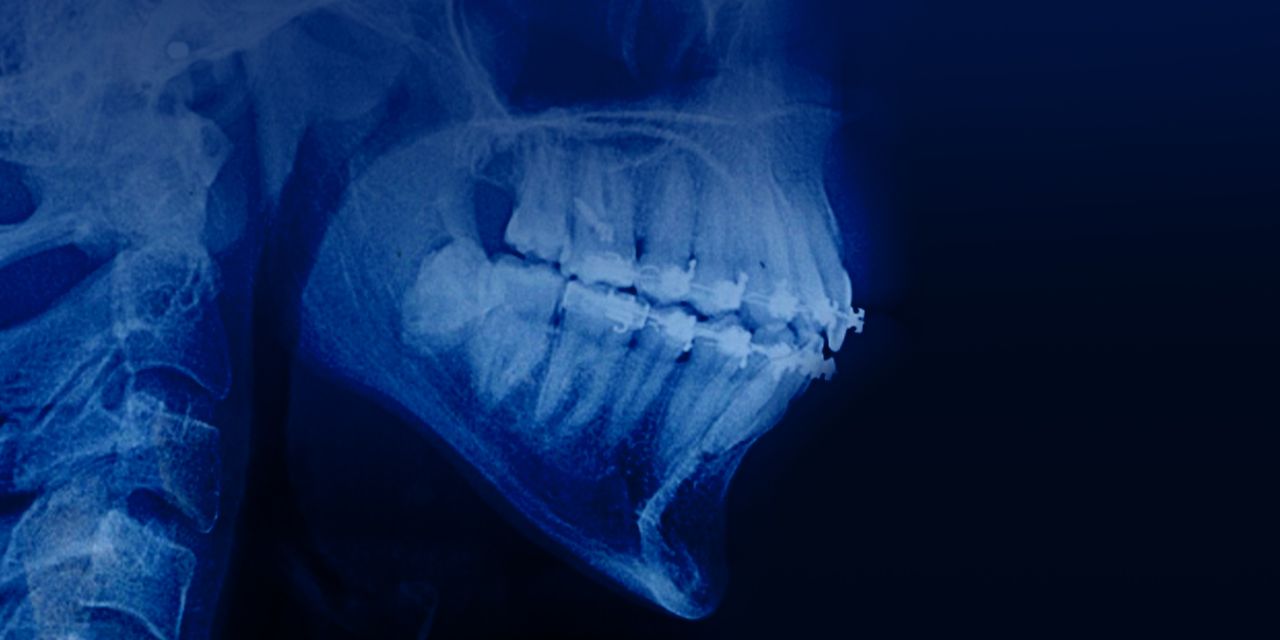

Дистализация моляров нижней челюсти: лечение сложных случаев скученности и мезиального прикуса без удаления зубов